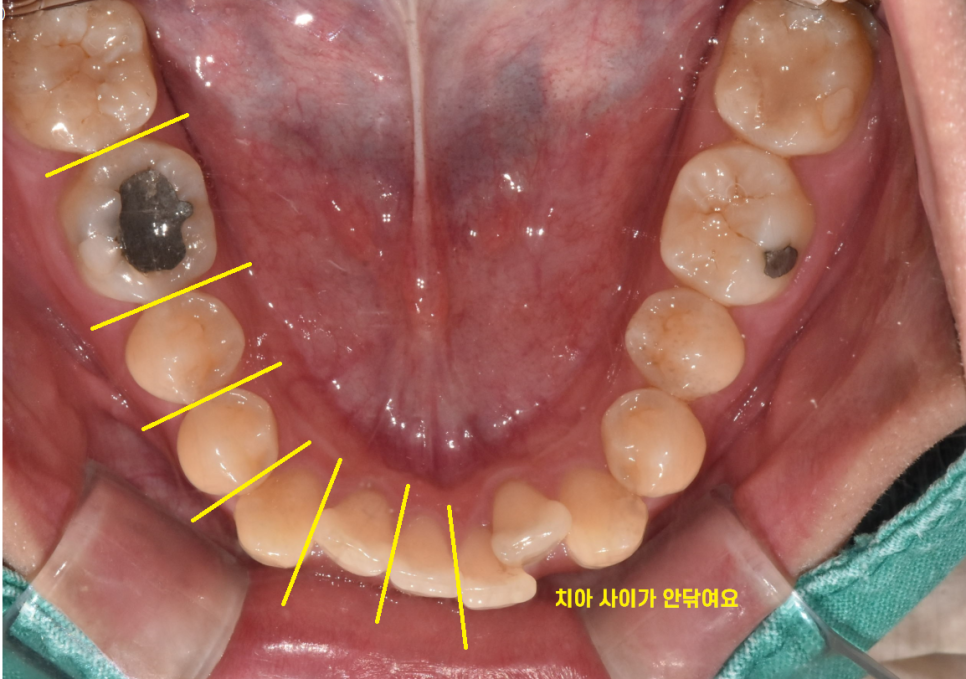

넓적한 부위는 닦이지만

치아 사이사이 부분은 칫솔모가 잘 들어가지 않아요~!

이 부위에 음식물 찌꺼기가 쌓이기 쉽고

이로인해 치아 사이에 충치가 생길 가능성이 높아집니다.

그래서 이런 경험 해보셨을꺼에요.

양치를 했는데 치실을 하면 음식물이 또 나오는!!